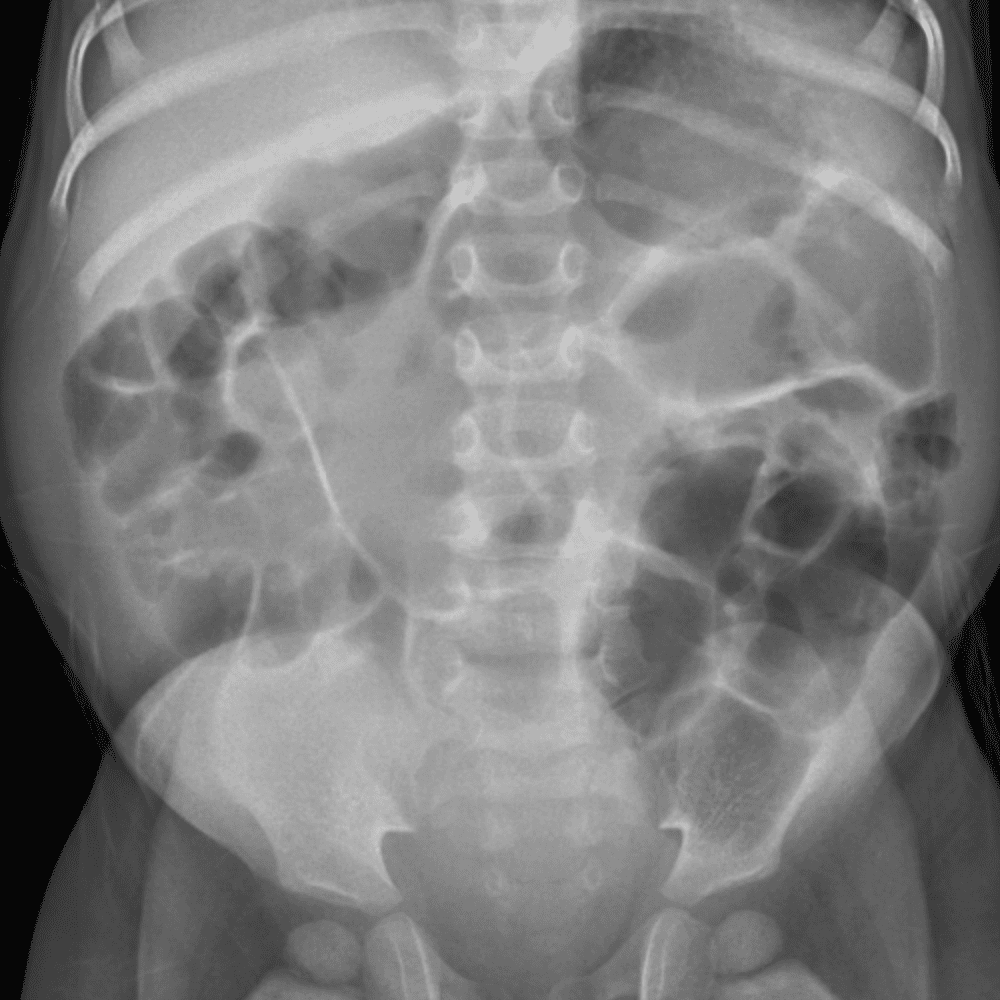

Peds Abdomen

Practice

Simulates call by including subtle or difficult cases and some normals.

30 cases